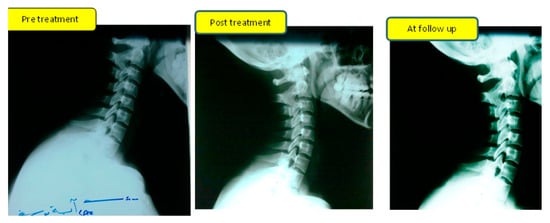

- Sagittal Cervical Alignment